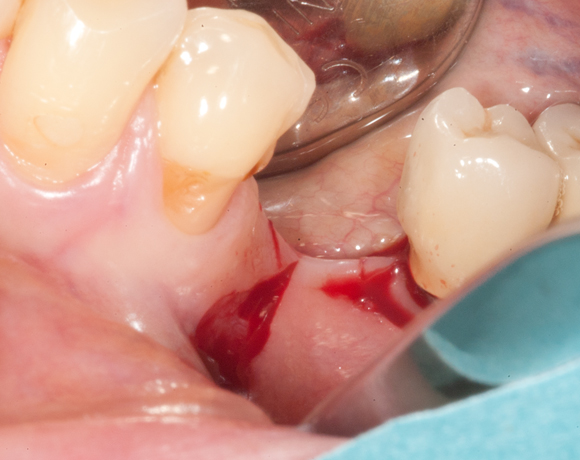

Im vorliegenden Fall war zwar eine gut Knochenhöhe vorhanden, jedoch war der Knochen zu schmal,

um Implantate aufzunehmen. Hier bietet es sich an den Knochen zu spalten, bei gleichzeitiger Insertion der Implantate und die freien Zwischenräume mit Kunstknochen aufzufüllen. Die Augmentation wird mit einer Membran abgedeckt. Die Einheilzeit beträgt sechs Monate.